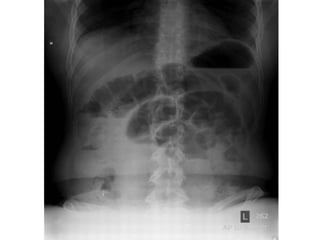

• La triada clásica de

obstrucción en el examen

radiológico es:

o Asas de intestino delgado dilatadas

(mayores a 3 cm)

o Niveles hidroaéreos

o Ausencia de aire distal

Signo del “grano de café”

Hallazgo clásico y diagnóstico del vólvulo sigmoideo en una radiografía simple de abdomen

El diagnóstico seconfirma mediante estudios radiológicos SERIE ABDOMINAL Rx abdomen paciente en posición supina Rx tórax Rx abdomen con enfermo de pie SENSIBILIDAD DEL 70 AL 80%

• La triadaclásica de obstrucción en el examen radiológico es: o Asas de intestino delgado dilatadas (mayores a 3 cm) o Niveles hidroaéreos o Ausencia de aire distal

Signo del “granode café” Hallazgo clásico y diagnóstico del vólvulo sigmoideo en una radiografía simple de abdomen